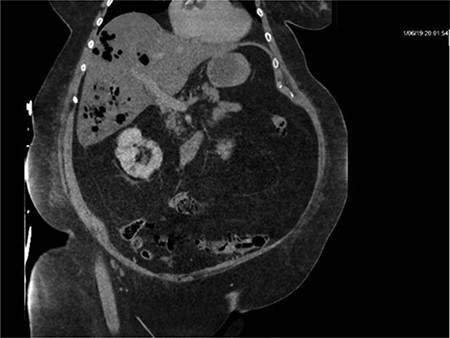

Repeat CT demonstrated a large amount of air within the liver parenchyma (Figs 2, 4, 6). Unfortunately, shortly after the repeat CT, the patient progressed to septic shock with cardiovascular collapse and was not able to be resuscitated with full advanced cardiac life support (ACLS) protocol. She expired within 16 h of initial presentation and within 24 h of symptom onset. Final blood culture results were positive for Clostridium perfringens.

Repeat imaging taken 13.5 h later which depicts many air bubbles in the liver parenchyma.